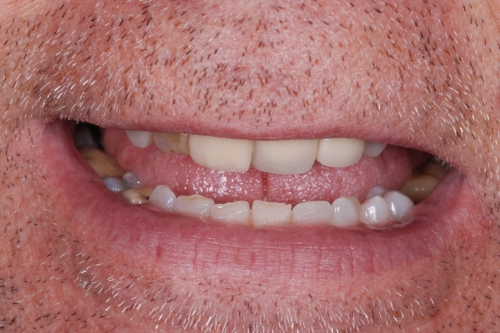

Sometimes, a tooth that’s had previous root canal treatment becomes reinfected or fails to heal as expected. Our advanced training and equipment allow us to manage these complex re-root canal cases, including:

- Removal of old root fillings, posts, or fractured instruments.

- Bypassing blockages and negotiating difficult anatomy.

- Managing ledges or obstructions within the canal.

- Treating teeth with silver points or unusual materials.

We’ll thoroughly assess your tooth, explain the reasons for failure, and discuss all available options, including whether retreatment is the best approach. Even if some obstructions can’t be removed, retreatment can still be successful, and we’ll always tailor our plan to your individual needs.